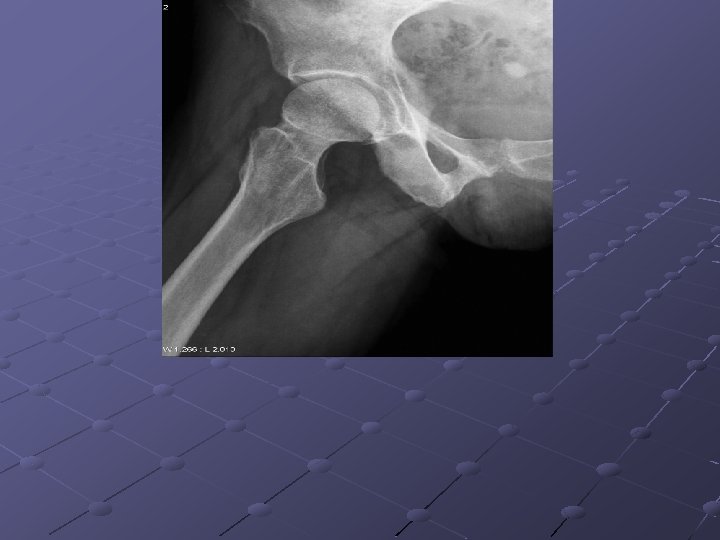

Imaging Studies